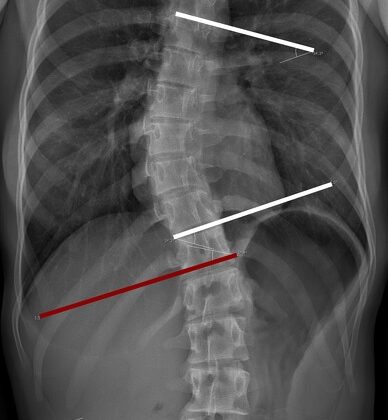

زاوية كوب هي المقياس الطبي الأساسي المستخدم لتحديد شدة اعوجاج العمود الفقري. يقوم الطبيب بقياسها باستخدام الأشعة السينية لتحديد مقدار الانحناء الجانبي للعمود الفقري بالدرجات.

بالتالي، فإن أي تغيّر في زاوية كوب مع العمر يحمل أهمية كبيرة في الخطة العلاجية.